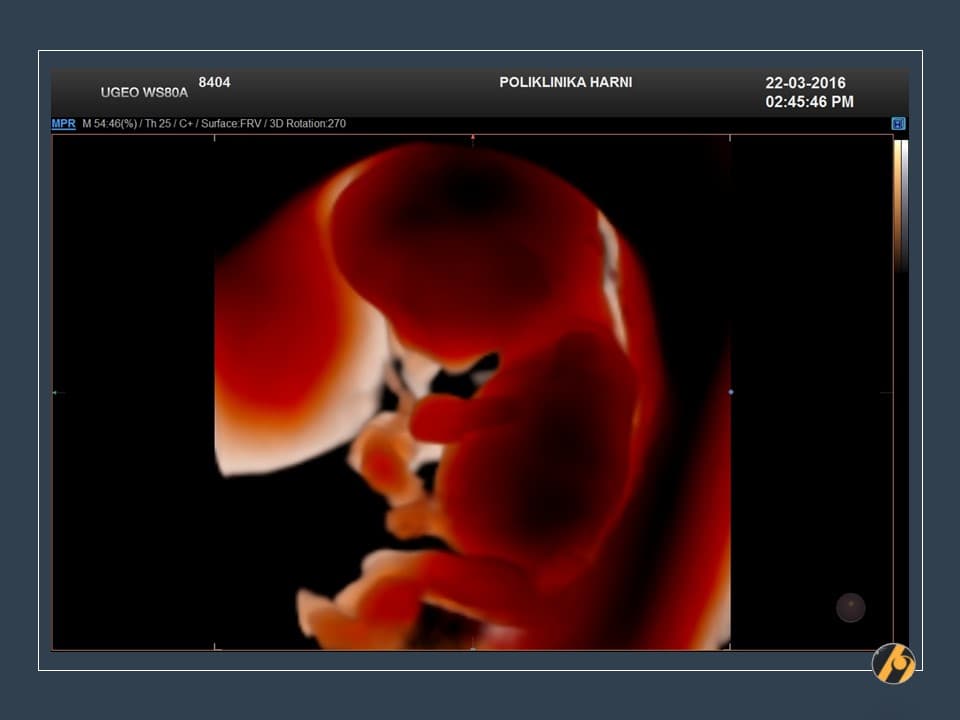

Glava vaše bebe još uvijek svojom veličinom nadmašuje tijelo, i čini gotovo cijelu polovicu dužine tijela. Razlog tomu je veoma rani početak razvitka mozga. Sada se uši postupno premještaju od vrata prema njihovom mjestu na glavi.

Napreduje razvitak ostalih organa. U trbuhu se intenzivno razvijaju crijeva, koja se nerijetko mogu vidjeti ultrazvučno i u pupčanoj vrpci / fiziološka omfalokela što je za ovaj period embriogeneze sasvim u redu. Crijeva se tijekom narednog tjedna vraćaju sasvim na svoje mjesto, u trbuh.

Vaša beba dugačka je 4.5 - 6.0 cm, a teška je 8 - 10 g.